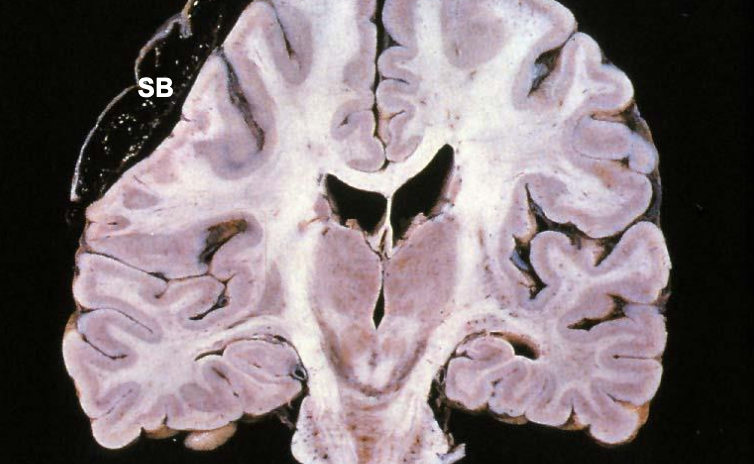

Huntington Disease

* Autosomal dominant * Bad Huntington gene * CAG triplet repeats * Polyglutamine inserts * Caudate and putamen atrophy * Chorea and dementia

43

Huntington's